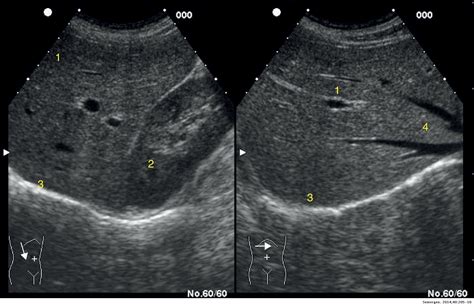

Interpreting the results of a Parenquima Hepatico Izquierdo Ecografia involves analyzing the ultrasound images for any abnormalities in the left hepatic parenchyma. Common findings include:

• Hepatic Lesions: These can be benign or malignant and may appear as cysts, tumors, or nodules.

• Fatty Liver Disease: Characterized by the accumulation of fat in the liver, which can appear as a bright, echogenic pattern on ultrasound.

• Liver Cirrhosis: Advanced liver disease that can show signs of fibrosis, nodularity, and altered liver texture.

• Hepatic Vascular Abnormalities: Such as portal vein thrombosis or hepatic vein obstruction.